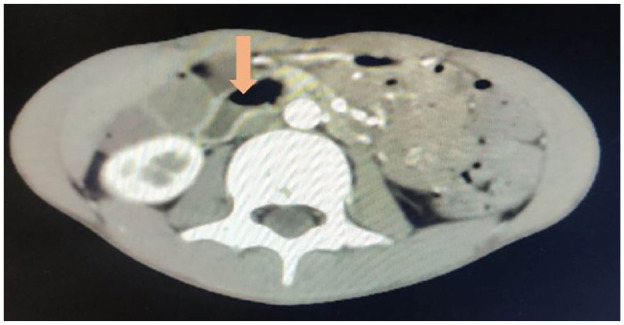

肠系膜上动脉综合征(SMAS)是一种因肠系膜上动脉压迫十二指肠而引起的罕见病症,但有可能危及生命。我们报告了一例 11 岁男性病例,他主诉腹痛和间歇性呕吐已持续 3 周。在放射学检查结果的帮助下,确诊为 SMAS。患者接受了营养支持、促动力药和胃减压等保守治疗。治疗两周后,患者的症状有所改善,康复出院。

Superior Mesenteric Artery Syndrome (SMAS) is a rare but potentially life-threatening condition caused by the compression of the duodenum by the superior mesenteric artery. We report a case of an 11-year-old male who complaint of abdominal pain and intermittent vomiting for last 3 weeks. Diagnosis of SMAS was made with the help of radiological findings. The patient was managed conservatively with nutritional support, prokinetic agents, and stomach decompression. After 2 weeks of treatment, the patient's symptoms improved, and he was discharged from the hospital.